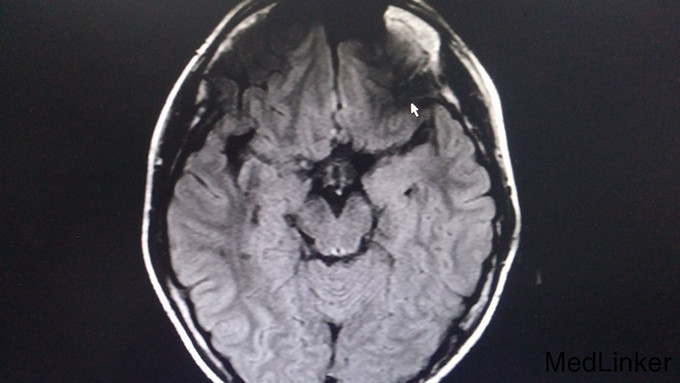

查体:脑膜刺激征阳性:Kernig征阳性,颈抵抗,颏胸距4指。辅助检查: 1. 血常规:白细胞19.02G/L,中性粒91.4%,血沉26mm/h;凝血6项纤维蛋白原4.08g/L,D-二聚体1.31mg/L;生化八项、脑脊液常规、生化、细菌、真菌未见明显异常,脑压240mmH20; 2. 脑电图:痫样放电,中度异常脑电图; 3. CT:双侧额叶纵裂旁灰质、双侧岛叶、右额叶上部及左顶叶多处灰质异常信号。 4. 外院T-spot试验阳性。